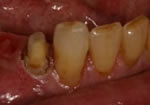

In many cases of dental decay, tooth fracture, or even in instances where an individual has "short" teeth, a crown lengthening procedure will allow us to properly construct an esthetic and functional crown, bridge, or restoration. Crown lengthening is a simple surgical procedure which adjusts the position of the gum around the affected tooth, thereby providing a more solid tooth on which to anchor the restoration of choice. A functional crown lengthening will help you regain a beautiful smile and allow you to eat and speak with comfort and confidence. A purely esthetic crown lengthening procedure to correct a "gummy" smile is often referred to as Gum Contouring.